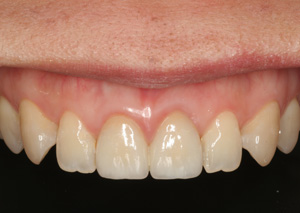

Clinical Cases